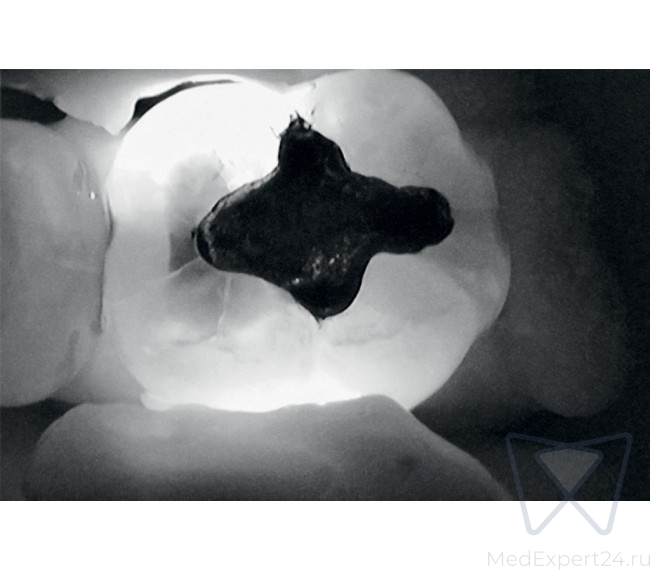

KaVo DIAGNOcam дает Вам полную уверенность в точности результата диагностики. С его помощью Вы сможете обнаружить кариозные поражения на самом раннем этапе развития.

KaVo DIAGNOcam позволяет визуализировать их на аппроксимальных и окклюзионных поверхностях зубов и обеспечивает проведение диагностики вторичного кариеса (при небольшом размере пломбы).